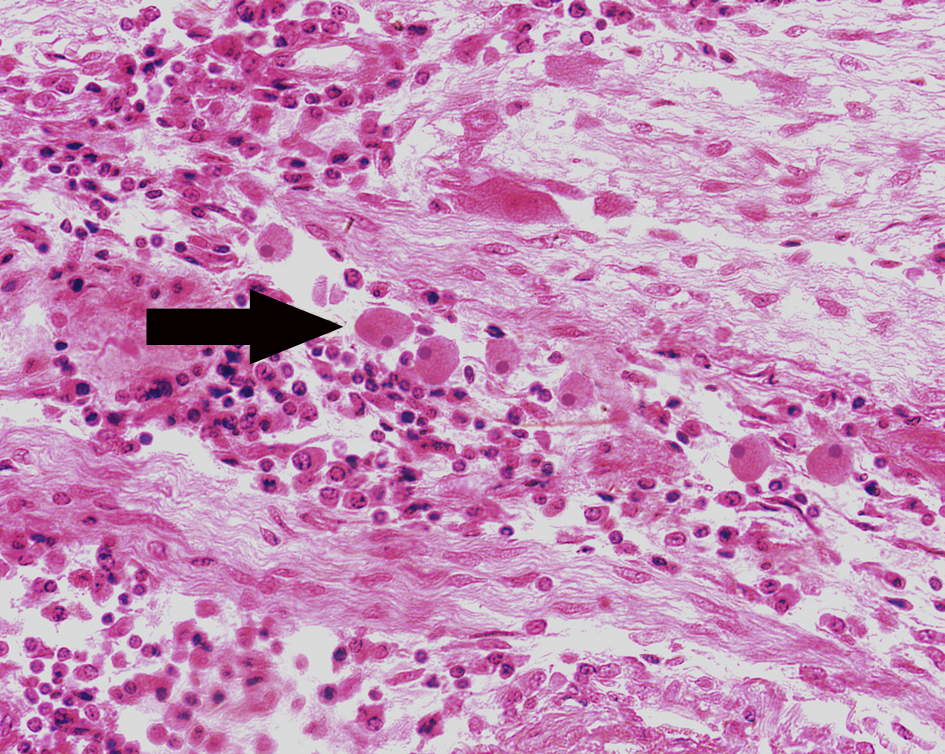

1.Amebic colitis